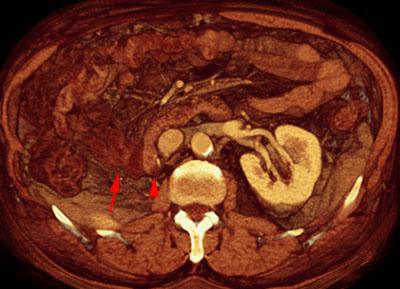

VR seccional. Visión axial caudal. En este TC contrastado se aprecia una ausencia del riñon derecho por nefrectomia radical y una ocupación de la fosa renal derecha por la segunda porción duodenal (punta de flecha) y por asas intestinales ileales (flecha)